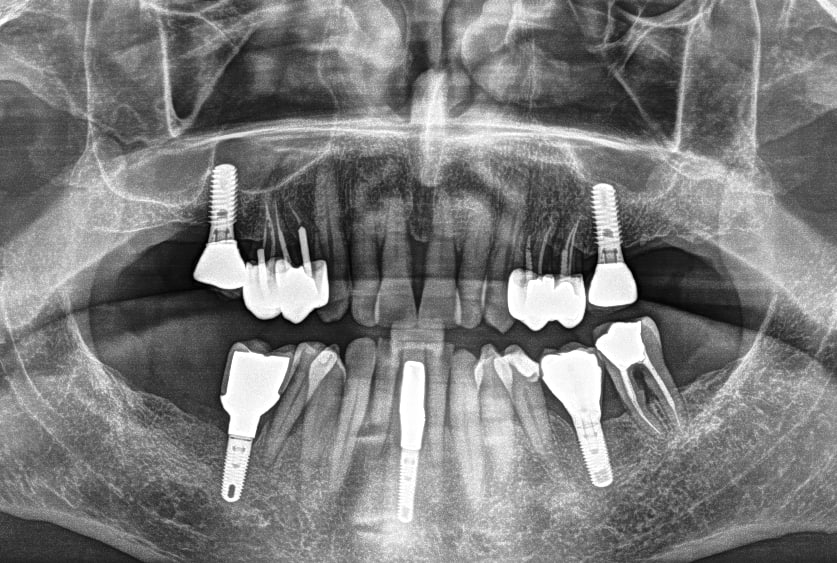

Pano la semaine dernière et inspection des 5 implants (l'autre pano date de l'été 2020). J'ai posé les 3 du bas il y a 7 ans. Les 2 du haut ont plus de 25 ans (ils n'apparaissent pas sur le dossier informatique qui débutent en 1997)

A la sonde, c'est la 16 qui est la plus atteinte. 41 et 46 stables.

Ce matin, j'ai nettoyé 41 et 46 (curetage, passage du prophyjet et etching pour faire bouillonner la zone plusieurs fois, je referme quand l'os est propre, sans résidu). Il reste de l'os en L de 41 (quasiment tout la hauteur) et à moitié sur la 46. Dans 15 jours j'attaque le haut.

Pour la tentative de traitement je te soutiens, de ce que tu dis et ce que je vois à la radio, il reste 3 parois en comptant les 2 proximales autour des implants, tu peux espérer récupérer un peu d'os, et comme il ne faut pas grand chose pour tenir un implant, si tu stabilises c'est gagné. Surtout à 88 ans.